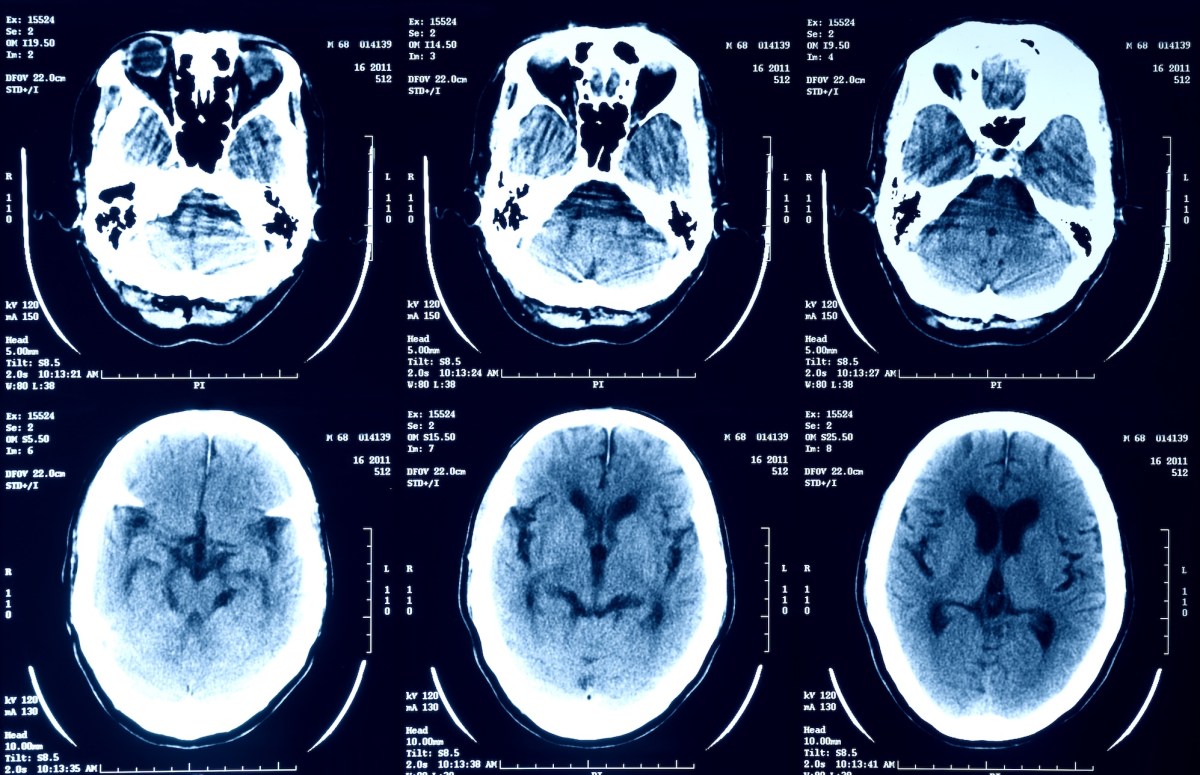

La gente recurre con frecuencia a chatbots de IA generativa, como ChatGPT de OpenAI y Gemini de Google, para hacer preguntas sobre sus preocupaciones médicas y comprender mejor su salud. Algunos se han basado en aplicaciones cuestionables que utilizan inteligencia artificial para decidir si los genitales de alguien están libres de enfermedades, por ejemplo. Y más recientemente, desde octubre, se ha alentado a los usuarios del sitio de redes sociales X a cargar sus radiografías, resonancias magnéticas y exploraciones PET al chatbot de inteligencia artificial Grok de la plataforma para ayudar a interpretar sus resultados.

El propietario de X, Elon Musk, que en una publicación animó a los usuarios para cargar sus imágenes médicas en Grok, admitió que los resultados de Grok están «aún en una etapa temprana», pero que el modelo de IA «será extremadamente bueno». Al pedir a los usuarios que envíen sus imágenes médicas a Grok, el objetivo es que el modelo de IA mejore con el tiempo y sea capaz de interpretar escaneos médicos con una precisión constante. En cuanto a quién tiene acceso a estos datos de Grok, no está claro; como anotado en otra parteGrok política de privacidad dice que X comparte información personal de algunos usuarios con un número no especificado de empresas «relacionadas».